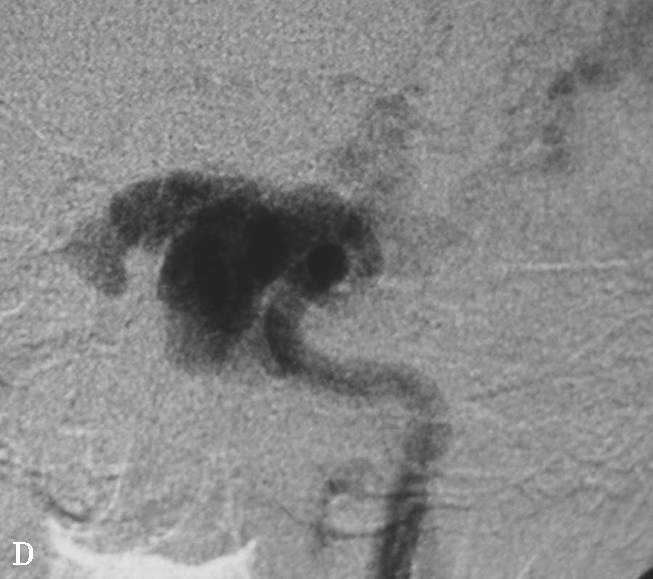

图1-2-6 左侧颈内动脉创伤后假性动脉瘤突入蝶窦

患者男,36岁,车祸伤后左侧额部硬膜外血肿清除并颅骨去骨瓣减压术后半年,间断大量鼻出血半个月就诊。A.颅脑CTA检查MPR横断面重组,可见蝶窦内软组织密度影,部分与颈内动脉同步均匀强化,并通过蝶窦骨质缺损与海绵窦游离段颈内动脉内侧壁相连,蝶窦内病变前缘部分未见强化;B.CPR(曲面重组)重建,示假性动脉瘤瘤体与邻近颈内动脉以宽基底相连,骨折断端与颈内动脉壁关系密切;C.CTA VR重建,示瘤体与左侧颈内动脉海绵窦段相连;D.左侧颈内动脉DSA检查可见海绵窦段假性动脉瘤显影,因瘤体盗血致其远端分支显影不满意